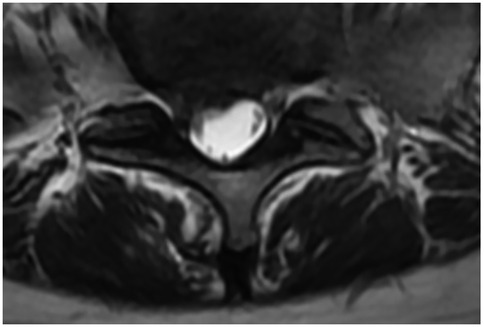

3.5 Typical case

This classic case involves a 71-year-old woman with degenerative lumbar scoliosis (coronal Cobb angle 18°, Figure 3A) who presented with low-back pain and right-leg numbness caused by right-sided L4–L5 lateral recess stenosis. Under general anesthesia she underwent precise decompression via a right interlaminar PEID approach, with an operative time of only 90 min and ∼30 ml blood loss, and no neural or dural complications; she was able to ambulate 6 h post-operatively. Pre-operative MRI (Figure 4A) vs. post-operative MRI (Figure 4B) shows adequate decompression. At 1-year follow-up her leg-and-back VAS had fallen to 1 point and ODI to 20%, while the Cobb angle remained 17° (Figure 3B).

Figure 4. Preoperative and postoperative axial T2-weighted MRI scans. (A) Preoperative image showing a herniated intervertebral disc (red arrow) compressing the nerve root. (B) Postoperative follow-up demonstrating adequate decompression, with the nerve root clearly released and no residual compression at the surgical level.